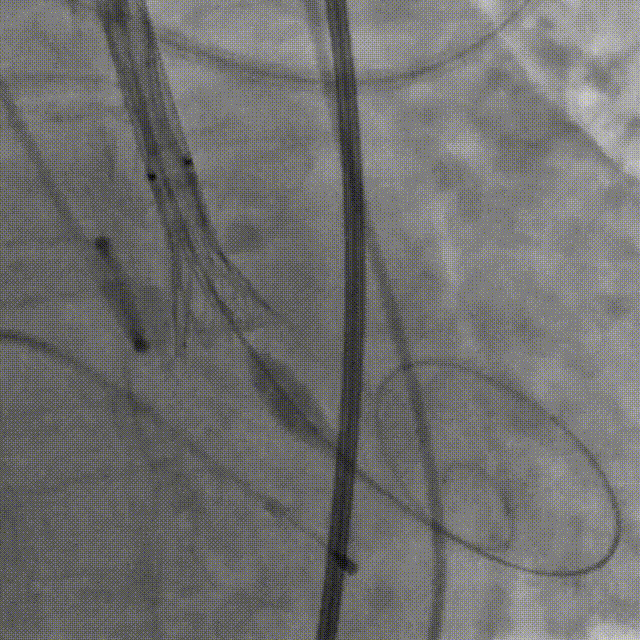

第一次释放,人工瓣膜受自体瓣膜挤压导致下滑

术中,人工瓣膜部分释放时,由于受自体瓣膜的挤压导致人工瓣膜下滑,陶主任立即对人工瓣膜进行了回收再定位,到达预期位置后精准释放,手术结果令人满意。